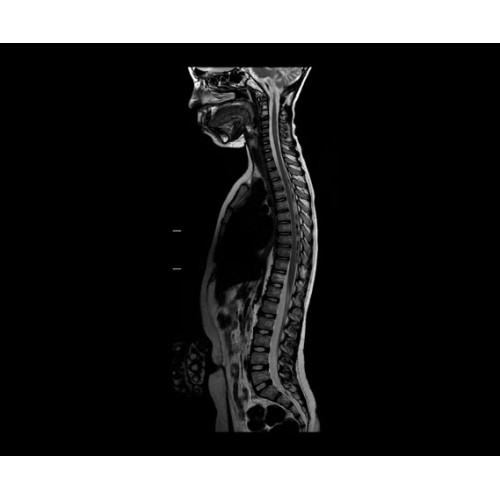

SIGNA Architect 3.0T — это новейший МРТ аппарат компании GE, который предлагает высочайший уровень производительности — в системе 128 приемных каналов, 48 канальная катушка головы, полный спектр клинических возможностей. Высокий уровень комфорта пациента обеспечивают такие особенности как отсоединяемый стол, положение пациента «ногами вперед» для всех видов исследований, SilentWorks — бесшумное и MAGIC — быстрое сканирование.

Теперь возможности МРТ поражают еще больше благодаря ультрасовременным решениям для визуализации с SIGNA Architect 3.0 Тл, объединяющей новейшие достижения в области МР-технологий и интуитивно понятный интерфейс. Система SIGNA Architect, разработанная на базе новой платформы SIGNA Works, представляет собой гармоничное сочетание дизайна и функциональности. Каждый элемент системы направлен на повышение производительности, эффективности клинической практики, финансовых показателей, а также комфорта и безопасности пациента.

Поле обзора 50x50x50 см и апертура шириной 70 см позволят достоверно визуализировать сложные анатомические области для пациентов с крупным телосложением, например, плечи и бедра. Феноменальная однородность системы SIGNA Architect обеспечивает наиболее широкое поле обзора с улучшенными характеристиками градиентов. Ничто не останется незамеченным.

• NeuroWorks — универсальное решение для визуализации анатомии головного мозга, позвоночника, сосудов и периферических нервов с четкой дифференциацией тканей.

• Digital Surround Technology (DST)— это новая технология объемной оцифровки данных, которая объединяет сигналы от каждого элемента катушки. Прекрасное соотношение сигнал/шум и чувствительность поверхностных катушек в сочетании с превосходной однородностью и высокой проникающей способностью встроенной радиочастотной катушки — все это позволяет создавать качественные изображения не только позвоночника, но и всего тела.